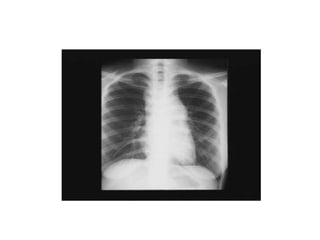

• Radiographie pulmonaire de face

1) Quels examensd’orientation demandez vous ? • Examen clinique complet avec schéma des adénopathies • NFP • VS ou CRP • Ionogramme sanguin complet • LDH • Bilan hépatique • Radiographie pulmonaire de face • Cytoponction ganglionnaire • Sérologies virales : MNI, HIV, toxoplasmose